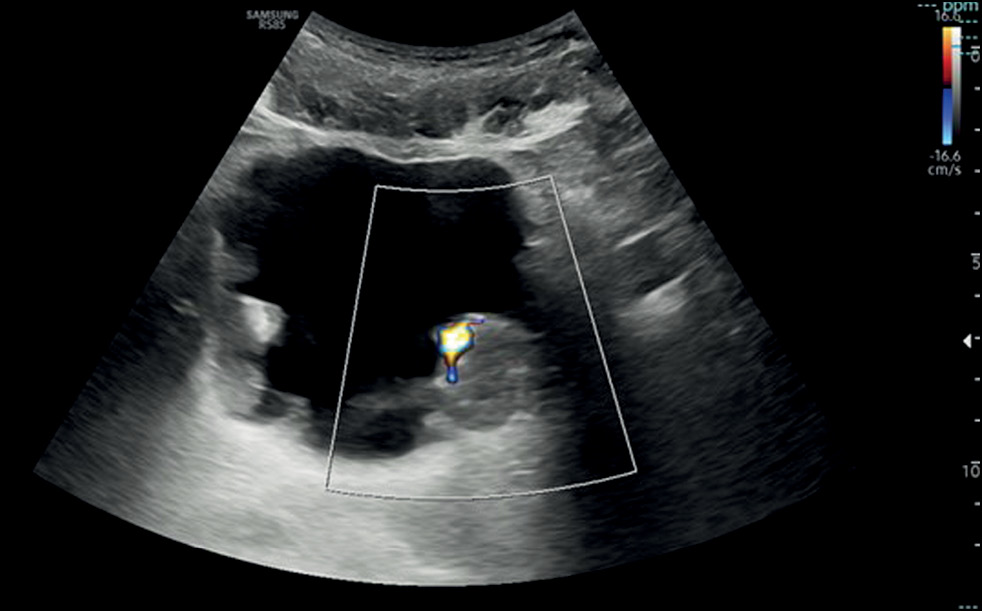

This narrative review describes the current status of imaging in the evaluation of bladder cancer, considering conventional technologies such as ultrasonography, computed tomography urography, and magnetic resonance imaging, as well as novel technologies such as contrast-enhanced ultrasonography and dual-energy computed tomography.

Imaging plays a critical role in the detection and staging of bladder cancer. In particular, the role of magnetic resonance imaging is expanding because it enables differentiating muscle-invasive bladder cancer from non-muscle-invasive bladder cancer using the Vesical Imaging-Reporting and Data System (VI-RADS), along with conventional technologies, such as computed tomography urography and ultrasonography. Contrast-enhanced ultrasound and dual-energy computed tomography are new imaging modalities that offer special advantages and provide the right approach to patients with oncological conditions. This review ends with the presentation of integrated imaging modalities such as positron emission tomography combined with computed tomography or magnetic resonance imaging, which are promising methods for bladder cancer staging.

- Liu Q, Gong H, Zhu H, Yuan C, Hu B. Contrast-Enhanced Ultrasound in the Bladder: Critical Features to Differentiate Occupied Lesions. Comput Math Methods Med. 2021;2021:1–5. doi: 10.1155/2021/1047948